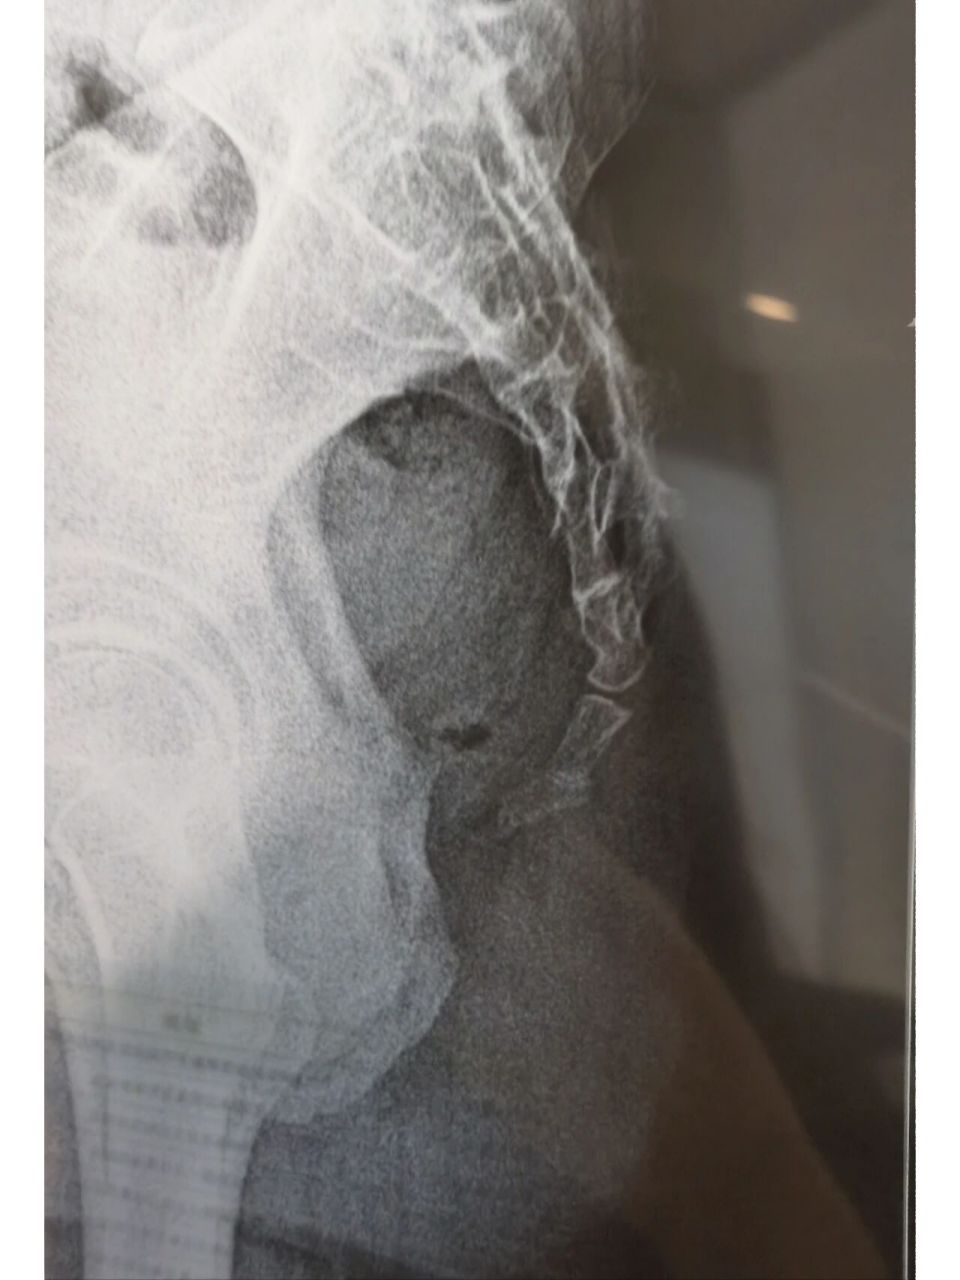

尾椎骨折

尾椎骨骨折 滑雪尾椎骨摔移位,怎么办,不滑了,收摊了